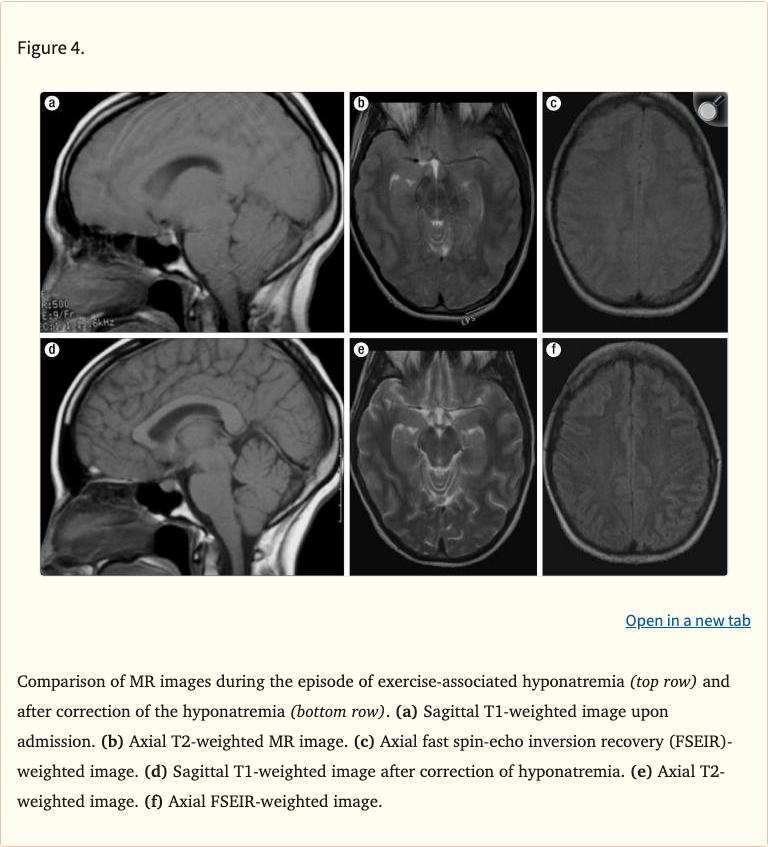

Figures